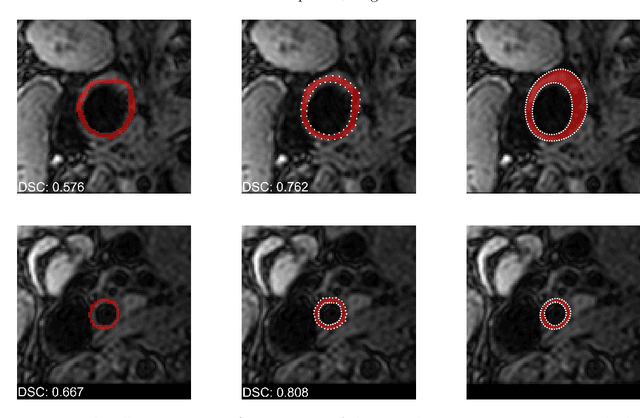

Abstract:Carotid artery vessel wall thickness measurement is an essential step in the monitoring of patients with atherosclerosis. This requires accurate segmentation of the vessel wall, i.e., the region between an artery's lumen and outer wall, in black-blood magnetic resonance (MR) images. Commonly used convolutional neural networks (CNNs) for semantic segmentation are suboptimal for this task as their use does not guarantee a contiguous ring-shaped segmentation. Instead, in this work, we cast vessel wall segmentation as a multi-task regression problem in a polar coordinate system. For each carotid artery in each axial image slice, we aim to simultaneously find two non-intersecting nested contours that together delineate the vessel wall. CNNs applied to this problem enable an inductive bias that guarantees ring-shaped vessel walls. Moreover, we identify a problem-specific training data augmentation technique that substantially affects segmentation performance. We apply our method to segmentation of the internal and external carotid artery wall, and achieve top-ranking quantitative results in a public challenge, i.e., a median Dice similarity coefficient of 0.813 for the vessel wall and median Hausdorff distances of 0.552 mm and 0.776 mm for lumen and outer wall, respectively. Moreover, we show how the method improves over a conventional semantic segmentation approach. These results show that it is feasible to automatically obtain anatomically plausible segmentations of the carotid vessel wall with high accuracy.